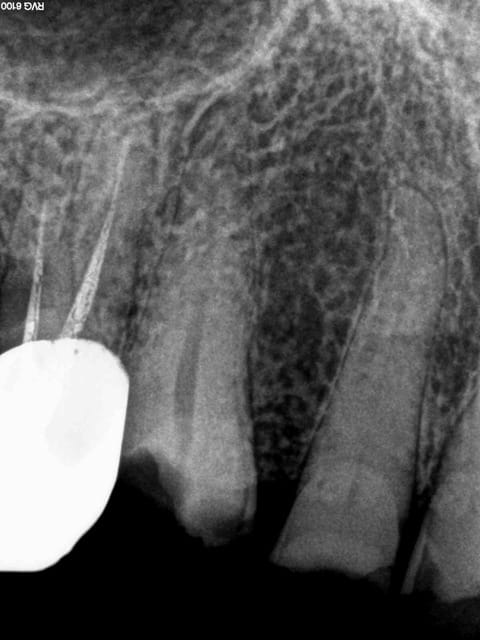

La dent que présente Chicot est pas blanc-bleue.

Bien délabrée

Archi-calcifiée

Un peu fêlée en mésial

Je pense pas qu'il ira aux Assises pour cette dent s'il prend la liberté de faire une endo.